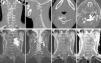

A rare case is presented of a left para-spinal chordoma, of which less than 10 cases have been reported in literature. It was located at C2-C4 level in a young male with no personal history of interest. Radiographic findings suggested that this was a slow-growing tumour, of cystic dominance, which eroded the bone structures and encompassed the left vertebral artery. Surgical excision was performed, and in the analysis of the surgical piece, cell proliferation was observed, with a stromal myxoid-chondroid appearance, epithelioid and physaliphorous (PAS+) cells, all of them compatible with chordoma.